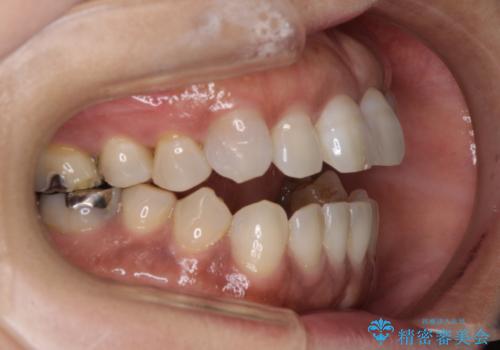

開咬の治療は、前歯を閉じるように動かすとともに、上下臼歯を圧下(骨内にめり込ませる)させることで進めて行きます。

インビザラインは臼歯の圧下を効果的に行えるため、インビザラインを用いて矯正治療を行うこととしました。

また、下顎大臼歯に根管治療が必要な歯があるため、矯正治療と並行して治療を行い、矯正後に補綴治療することとしました。